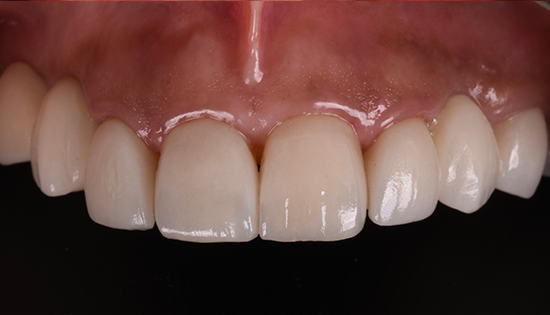

يلجأ الشخص إلى تحسين شكل أسنانه عن طريق فينير الأسنان أو ما يطلق عليه (عدسات الأسنان اللاصقة) وهي عبارة قشرة رقيقه يتم لصقها على السطح الخارجي للأسنان مصنوعة من مواد صلبة ذات معامل شفافيه مطابق للأسنان الطبيعيه   لعلاج مشكلة الاصفرار أو عدم التساوي والعديد من المشاكل الأخرى، حتى يحصل الشخص على ابتسامة رائعة تشبه ابتسامة نجوم هوليود.

• إظهار الأسنان بشكل أكثر جمالًا بعد تغطية كل عيوب الاسنان.

• نعتمد في تصنيع الڤينيرز علي طاقم فني من امهر الفنيين في الوطن العربي ولهم خبره طويله جداً في تجميل اسنان العديد من المشاهير.

• نستخدم في تصنيع الڤينيرز الخامات السويسريه التي تعد الأفضل والأشهر عالمياً .